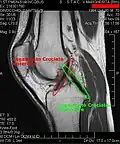

Os ligamentos são os estabilizadores primários para a translação anterior e posterior, angulação vara e valga, e para a rotação interna e externa da articulação do joelho. O ligamento cruzado anterior (LCA) é a restrição predominante ao deslocamento tibial anterior, pois aceita 75% da força em extensão completa e um adicional de 10% (até 90.º) de flexão do joelho. Com esses dados fica evidente que o LCA é o mais exigido no dia a dia de uma pessoa saudável, que pratica esporte por lazer ou profissão.

ligamento cruzado anterior (LCA) dentro côndilo lateral do fêmur área intercondilar anterior O papel do LCA é prevenir o deslizamento anterior excessivo da tíbia em relação ao fêmur

ligamento cruzado posterior (LCP) dentro côndilo medial do fêmur área intercondilar posterior A lesão deste ligamento é incomum, mas pode ocorrer resultando de uma força de tração traumática do ligamento. Este ligamento previne o deslizamento posterior excessivo da tíbia em relação ao fêmur.

Em esportes que impões muito impacto nos joelhos, especialmente forças de torção, é comum o rompimento de um ou mais ligamentos ou cartilagens do joelho. O ligamento cruzado anterior é frequentemente rompido como um resultado de uma rápida mudança na direção durante uma corrida ou como um resultado de algum outro tipo de movimento de torção violento. Ele também pode ser rompido com a extensão forçada além de sua amplitude normal, ou como resultado de forças sendo aplicadas lateralmente.[1]

As lesões ligamentares podem ocorrer como um resultado da força que faz com que a articulação exceda sua amplitude de movimento (ADM) normal. Uma pancada no aspecto lateral da articulação do joelho ou da tíbia pode causar um estresse em valgo que resulta no rompimento dos ligamentos impedindo movimento em valgo. Da mesma forma a hiperextensão forçada do joelho pode causar rompimento dos ligamentos posteriores. Embora forças excessivas possam causar rupturas ligamentares, força de baixa magnitude pode também causar rompimentos em ligamentos enfraquecidos pela idade, doença, imobilização, esteróides ou insuficiência vascular. Devido a esses problemas, um fortalecimento dos músculos desta complexa articulação, com a devida orientação postural, fará com que as pessoas sejam cautelosas e mais seguras na prática dos esportes tais como futebol, basquete e atletismo.

Antes do advento da artroscopia, os pacientes que faziam cirurgia para um LCA necessitavam de pelo menos nove meses de reabilitação. Com as técnicas atuais de reconstrução do LCA, estes pacientes podem hoje estar caminhando sem dificuldades em duas semanas, e praticando esportes em poucos meses.